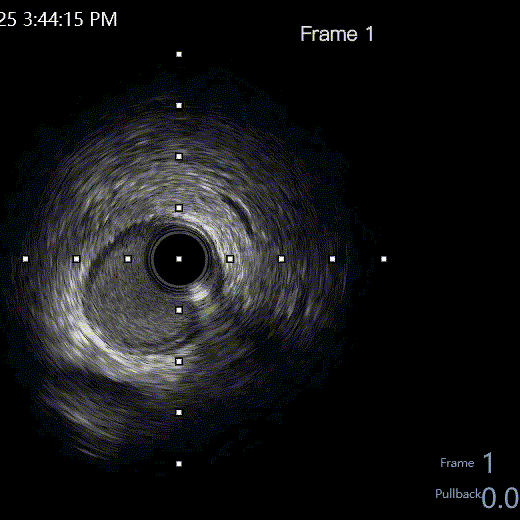

术前腔内影像学IVUS指导

IVUS提示血管可见钙化明显,为360°环形钙化。遂考虑启动IVL治疗。

IVUS提示LAD近中段钙化病变,中段可见360°环形钙化。

IVUS提示血管内钙化严重,最小管腔面积不足 4mm²;遂考虑启动IVL治疗。